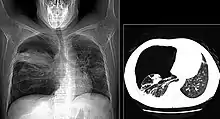

X-ray and CT of ground glass opacities and pneumothorax in pneumocystis pneumonia.[7]

Pneumothorax is a well-known complication of PCP.[8] Also, a condition similar to acute respiratory distress syndrome (ARDS) may occur in patients with severe Pneumocystis pneumonia, and such individuals may require intubation.[9]